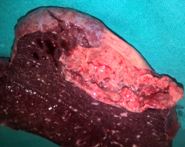

Liver after resection of the infected cyst. Presence of hemostatic Surgicel on the raw surface (Courtesy Dr. V. Penopoulos)